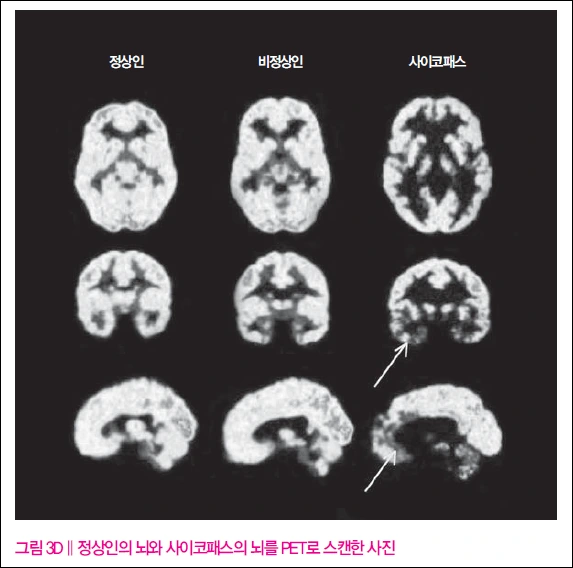

사이코패스의 뇌는 쉽게 이야기하면 불이 꺼진 길거리와 비슷합니다. 무서움을 담당하는 부분과 감정을 처리하는 부분이 완전히 꺼져있는 것이죠. 그렇기에 겁도 별로 없고. 감정에 대한 반응도 많이 하지 않습니다. 저자의 성장기를 책에서 과도하다 싶을 정도로 많은 부분을 할애한 이유도 그와 비슷하다고 생각합니다. 그의 인생을 통해 그가 아슬아슬하게 사이코패스와 정상인의 선을 넘나드는 모습을 잘 관찰할 수 있기 때문이죠.

PET 및 fMRI 사진 결과 그의 뇌가 놀랍도록 사이코패스들의 결과와 비슷하다는 것이 책에도 그림으로 실려있죠.(참고 3) 그리고 그 원인이 된다고도 할 수 있는 전사 유전자를 물려받았습니다. 그렇다면 세 개의 다리 중 두 개나 가지고 있는 저자가 우리나라로 치자면 9시 뉴스에 뻔질나게 등장하는 사이코패스 연쇄 살인마가 되지 않은 이유는 무엇일까요.

MRI와 X-ray 보는 법을 배우면 은근 재밌음. 비교도 할 수 있고 이게 이렇게 잘못되었군... 하면서 볼 수도 있는데 저 사진은 책에서 보자마자 소리 질렀음. 저자가 사실을 알고 나서 부정할 만 했음.